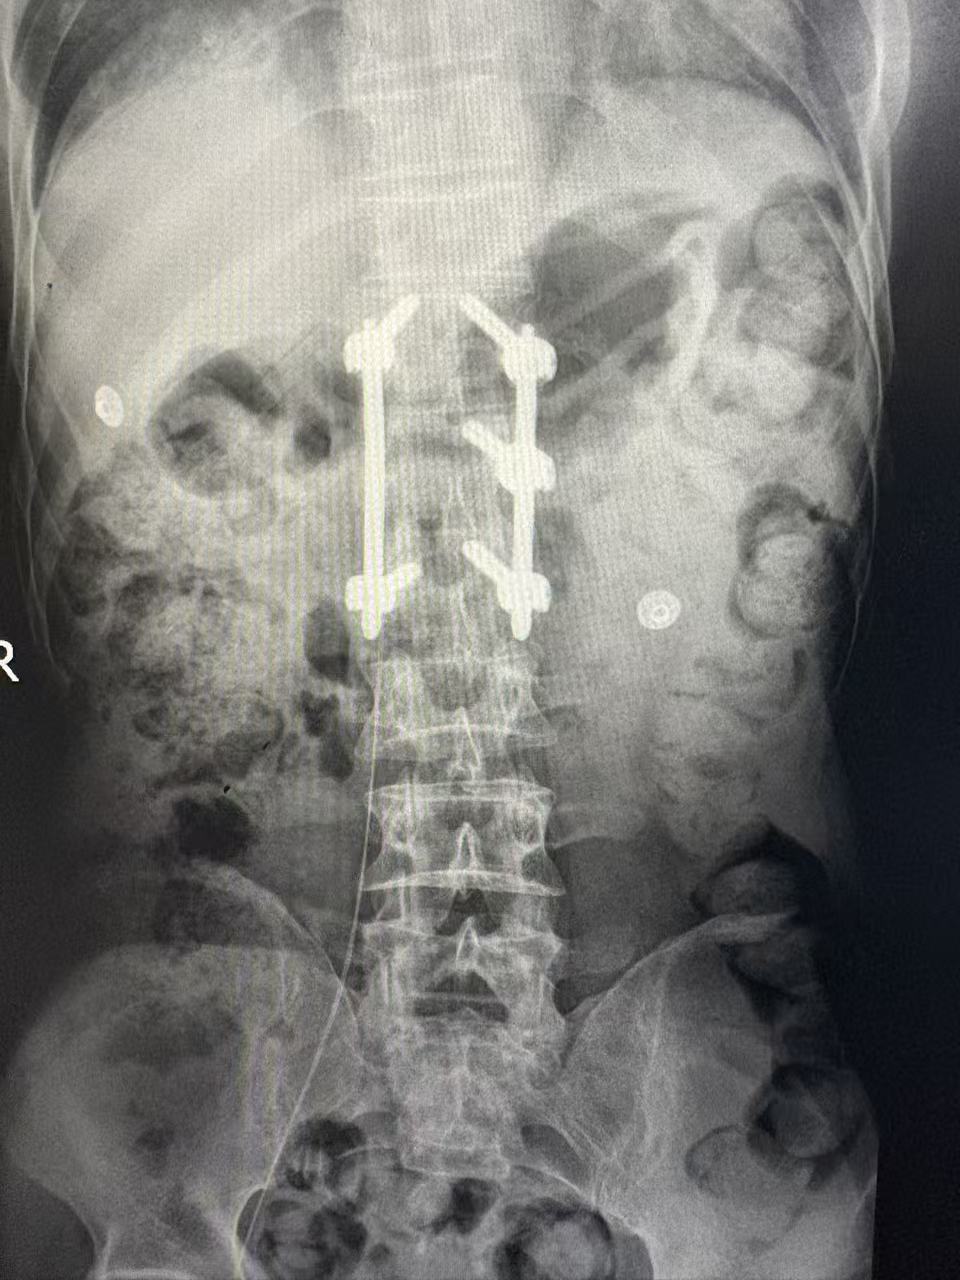

△置管中采用超声引导结合心电定位

面对这一棘手难题,南华医院肿瘤一区静脉治疗护理团队迎难而上,在科室主任唐三元教授及护士长欧娜的带领下,经过缜密的术前讨论和评估,果断决定为患者实施“经下腔静脉PICC置管术”。术中,团队凭借丰富的经验和娴熟的配合,在超声引导下精准穿刺患者的股静脉,并结合如同“GPS导航”一般的心电定位技术,清晰地指引着导管尖端准确到达理想位置,整个过程顺利,患者无特殊不适。这条经由股静脉建立的“生命通道”,成功绕开了被肿瘤压迫的“禁区”,为后续的化疗、营养支持等生命治疗提供了坚实保障。